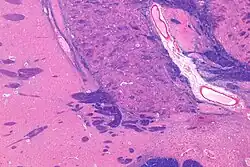

![]() Intermediate magnification micrograph of the nucleus basalis. LFB-HE stain. | |